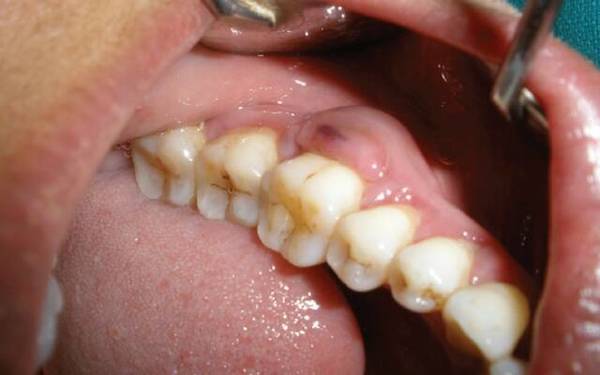

Абсцедирующий

Характеризуется появлением гнойного очага, то есть абсцесса. Эта форма пародонтита способна привести к атрофированию костной ткани.

Фото 3. Абсцедирующий пародонтит. В области коренных зубов наблюдается гнойный абсцесс и сильная припухлость.

Симптомы заболевания: кровоточивость десен, углубление пародонтального кармана до четырех миллиметров, подвижность зубов, возникновение болевых ощущений даже в состоянии покоя, появление гнойных мешочков.

Причины возникновения заболевания — зубной налет и камень, а также запущенный гингивит и другие патологии функционирования организма.

Чаще всего пораженный зуб удаляют, но в некоторых ситуациях возможно лечение без операции.